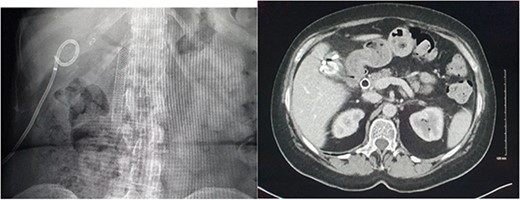

Right common femoral artery access was achieved, followed by Mickelson catheter access to celiac axis. Digital subtraction angiography (DSA) demonstrated active haemorrhage arising from the cystic artery (Fig. 2). A Renegade HiFlow microcatheter (Boston Scientific) was advanced into the cystic artery arising from the right hepatic artery. A repeat DSA in this position demonstrated multiple points of active haemorrhage around the gallbladder with two main branches arising from a central trunk. A single 3 × 3.3 mm Vortx coil (Boston Scientific) was deployed into the proximal cystic artery. A repeat DSA through the microcatheter in the right hepatic artery demonstrated the cessation of flow in the cystic artery and no further active haemorrhage (Fig. 2).

DSA images demonstrating active haemorrhage from the cystic artery and subsequent coil embolization with cessation haemorrhage.